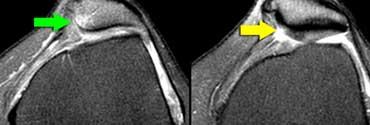

Viêm túi hoạt dịch dây chằng bên trong nằm giữa MCL sâu (mũi tên vàng) và MCL nông (mũi tên xanh lá).

Các túi hoạt dịch này đều được đặt tên theo các cấu trúc lân cận.

Do đó, viêm túi hoạt dịch nằm giữa MCL sâu và MCL nông được gọi là viêm túi hoạt dịch dây chằng bên trong.

Hình bên trái là một vận động viên đi bộ tốc độ cao với triệu chứng đau mặt ngoài gối.

Bình thường phải có mô mỡ giữa dải chậu chày và lồi cầu ngoài, nhưng trong trường hợp này mô mỡ không còn hiện diện.

Hội chứng ma sát dải chậu chày: Dịch trong túi hoạt dịch thấy được giữa dải chậu chày và xương đùi (mũi tên vàng). Dịch khớp dừng lại tại các mũi tên đỏ.